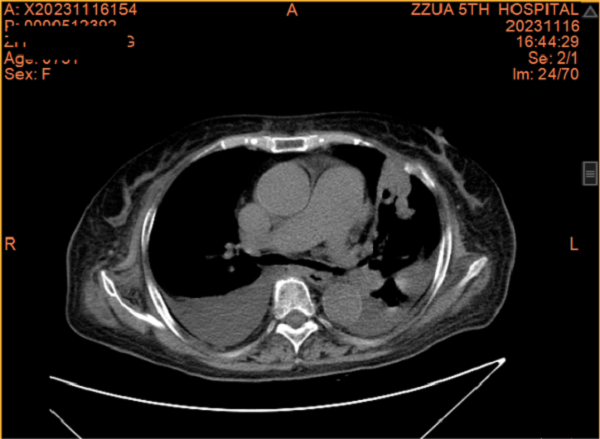

一个月前,张阿姨再发胸闷、心悸,这次张阿姨主动找到了全科医学科。住院期间因受凉出现鼻塞、流涕、发热,病情进展迅速,咳嗽、咳痰、胸闷、心悸、气喘等症状明显加重,动脉血气提示Ⅰ型呼吸衰竭并代谢性酸中毒。张阿姨精神特别差,情绪也十分低落。全科医学科主任刘培杰主任医师及别柏林主治医师综合分析病情后,第一时间给予碳青霉烯类积极抗感染、糖皮质激素抗炎、硝酸酯类扩张血管减轻心脏负荷、控制快速心室率、经鼻高流量湿化氧疗等综合治疗,护理团队给予饮食指导及心理辅导,张阿姨的病情很快得到控制,经复查胸部CT,肺部病变较前明显吸收,出院时再次对其慢性病管理及预防、治疗措施对其进行了再次的细致交代,病情好转出院。